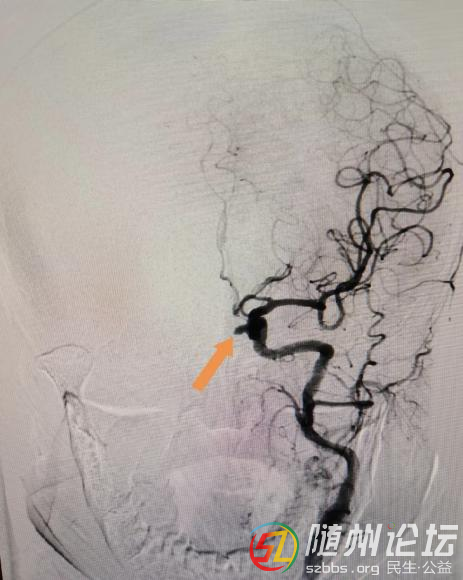

曾都醫(yī)院:精準(zhǔn)栓塞,守護(hù)大腦--介入下動脈瘤栓塞術(shù)為生命護(hù)航 近日,在武漢大學(xué)中南醫(yī)院但畢堂教授指導(dǎo)下,隨州市曾都醫(yī)院神經(jīng)內(nèi)科與介入科、麻醉科緊密配合,成功完成了4例介入下顱內(nèi)動脈瘤栓塞術(shù),其中2例為動脈 ...